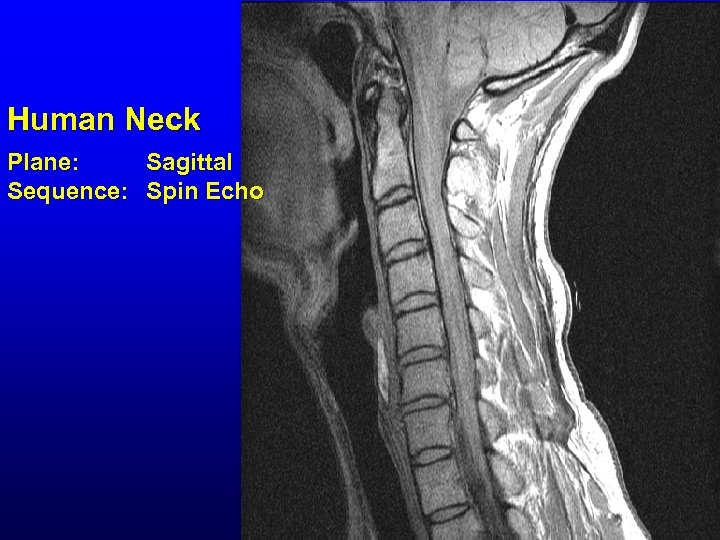

Human Neck Plane: Sagittal Sequence: Spin Echo